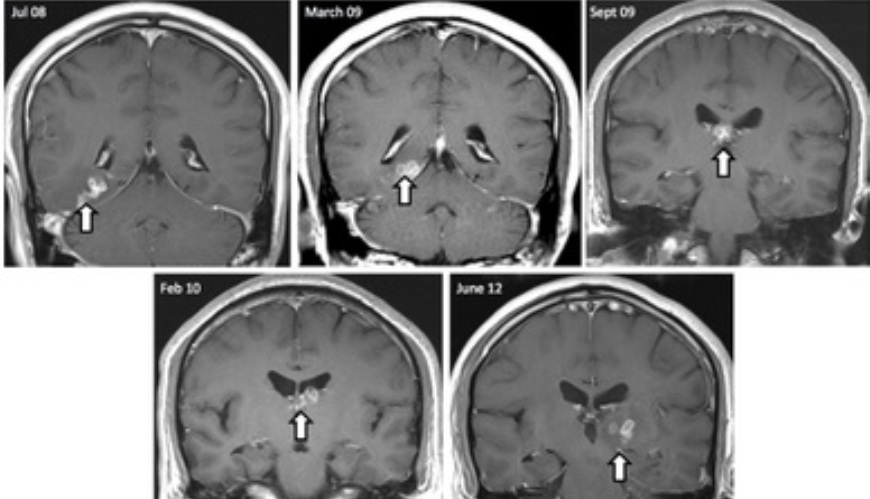

A través de una resonancia magnética se pudo determinar que su cerebro tenía una serie de lesiones. Sin embargo, los médicos desconocían las causas.

Pero durante los siguientes cuatro años se logró ver que las lesiones se desplazaron unos cinco centímetros del hemisferio izquierdo al derecho.

Después de numerosas pruebas y biopsas finalmente, en el año 2012, los médicos encontraron los restos de un gusano de unos 10 centímetros en el cerebro del hombre, quien fue tratado con medicina anti parasítica.